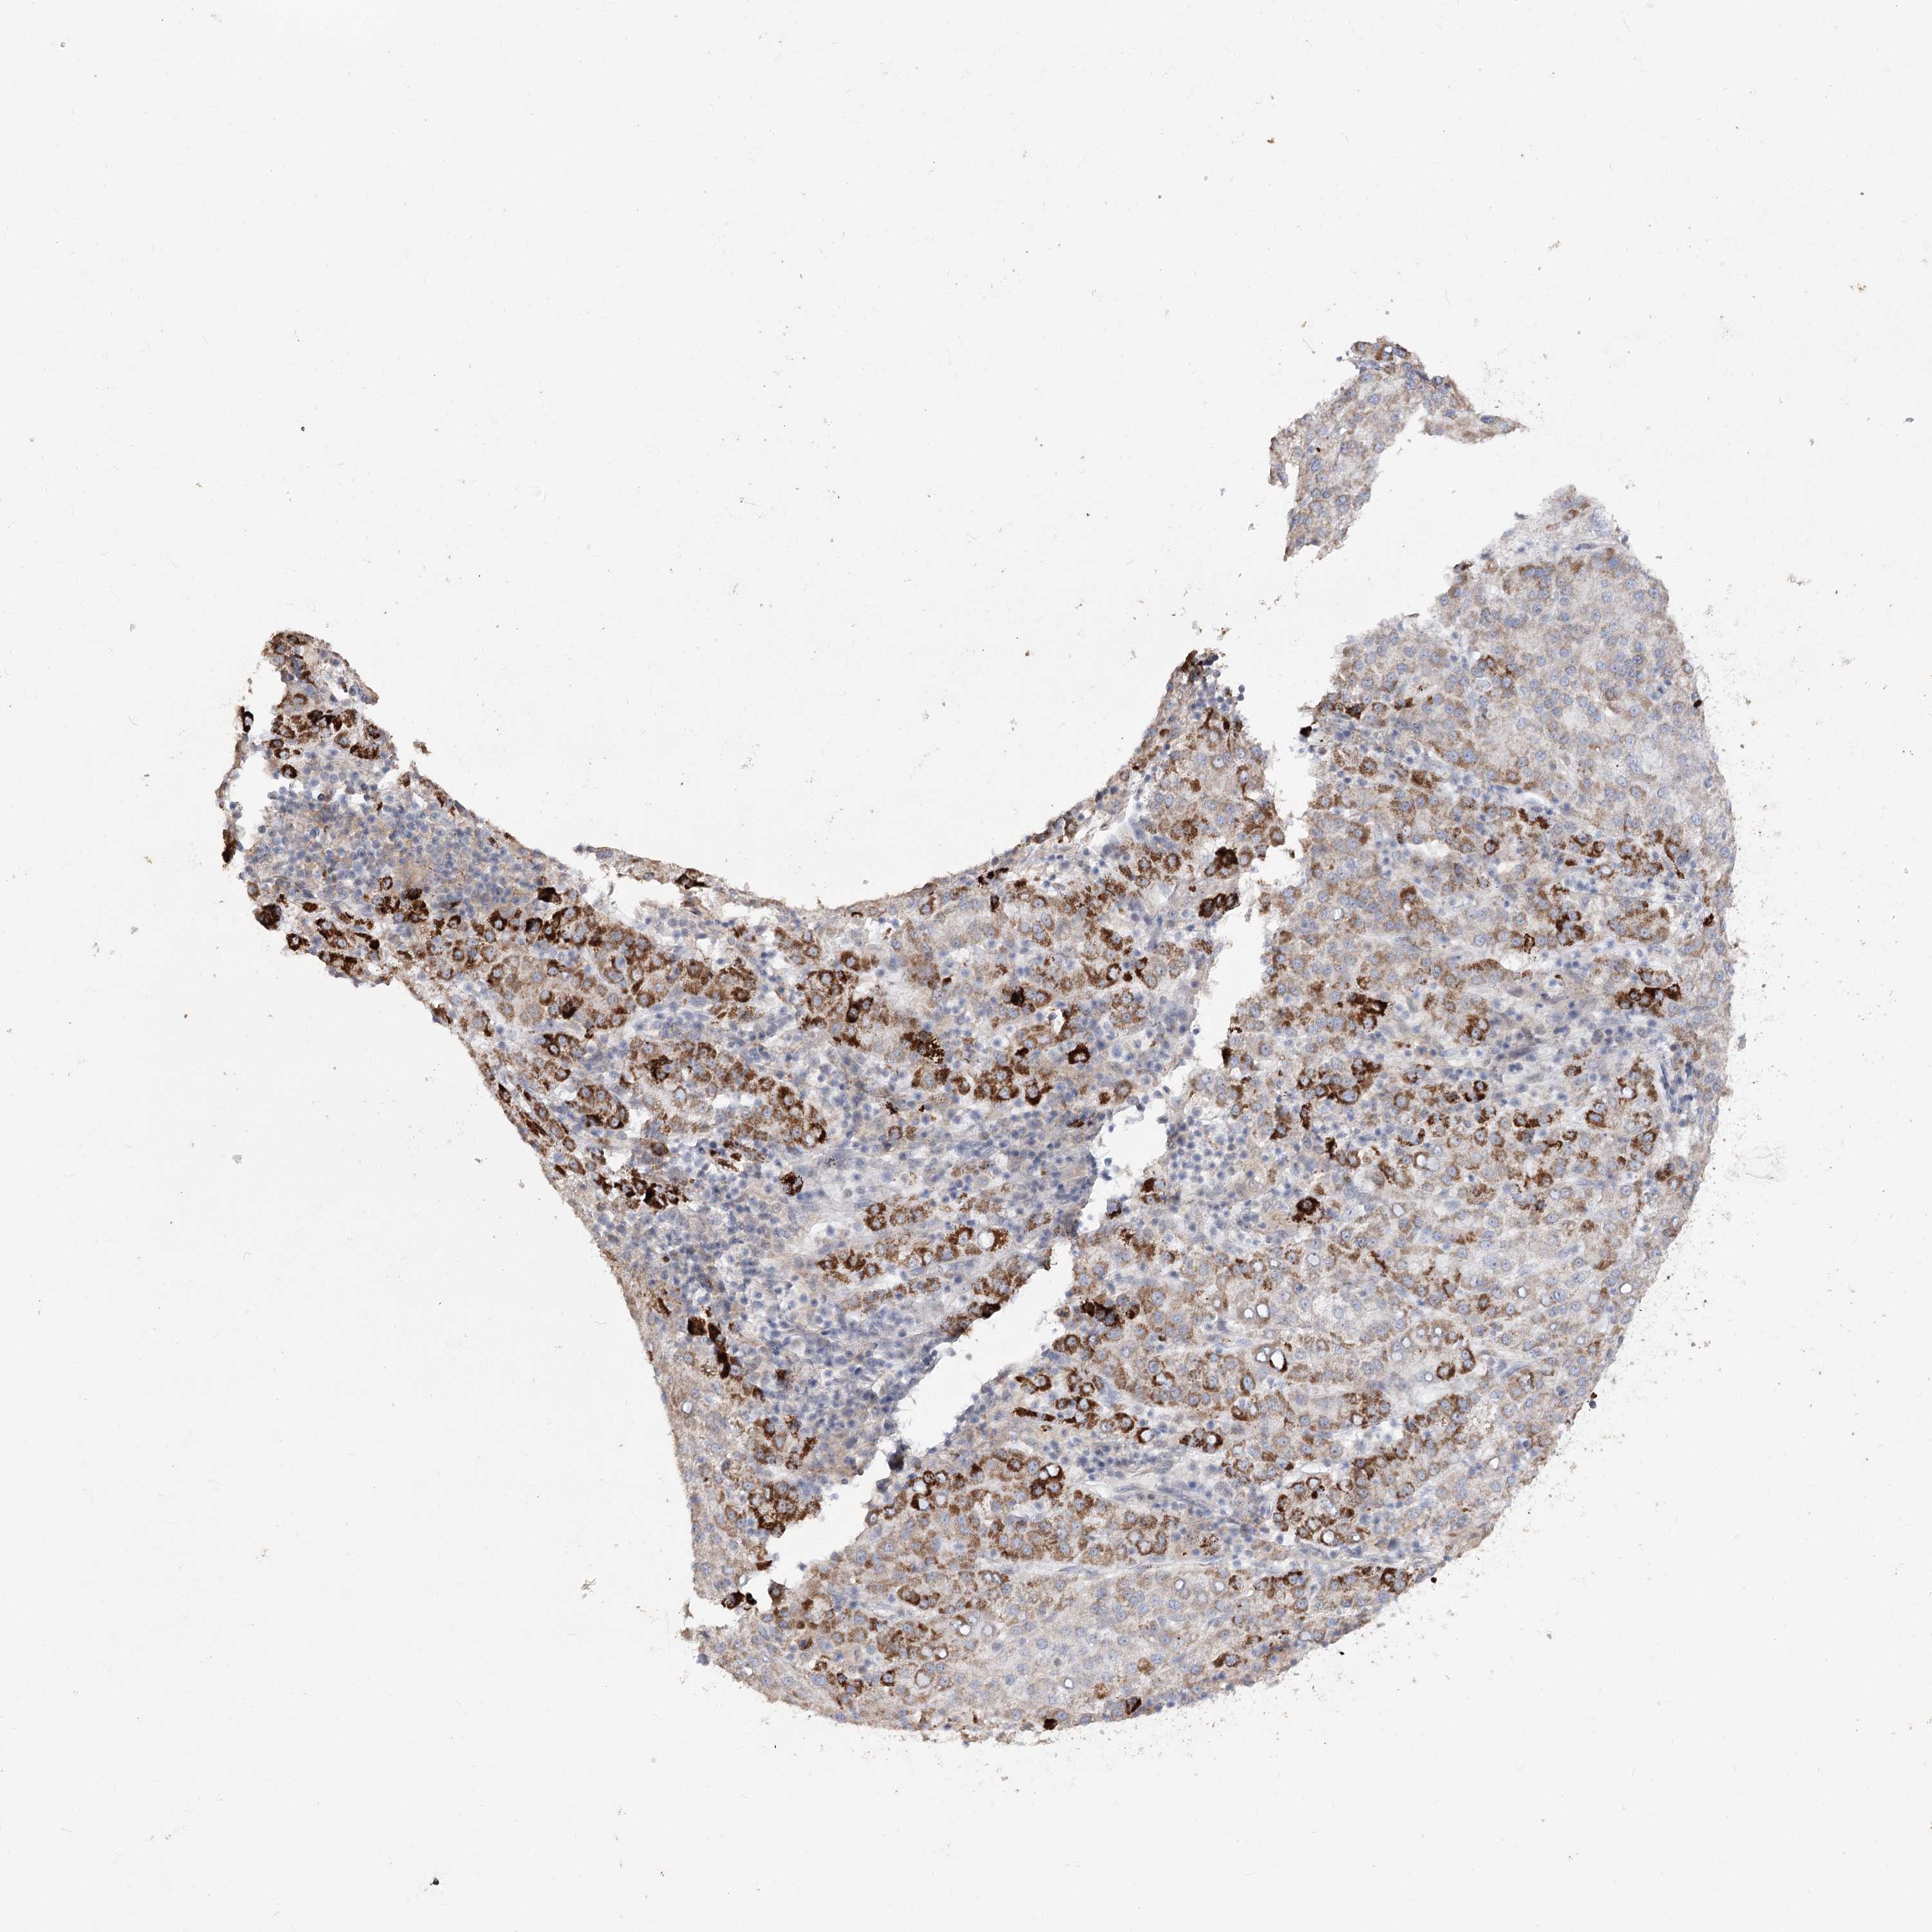

LIVER CANCER - Protein expressioni

A mouse-over function shows sample information and annotation data. Click on an image to view it in a full screen mode. Samples can be filtered based on level of antibody staining by selecting one or several of the following categories: high, medium, low and not detected. The assay and annotation is described here.

Note that samples used for immunohistochemistry by the Human Protein Atlas do not correspond to samples in the TCGA dataset.

Antibody stainingi

Antibody staining in the annotated cell types in the current human tissue is reported as not detected, low, medium, or high, based on conventional immunohistochemistry profiling in selected tissues. This score is based on the combination of the staining intensity and fraction of stained cells.

Each image is clickable and will lead to virtual microscopy that enables deeper exploration of all samples and also displays staining intensity scores, fraction scores and subcellular localization as well as patient and tissue information for each sample.

Antibody HPA035959

Antibody HPA035960

Staining

High

Medium

Low

Not detected

Intensity

Strong

Moderate

Weak

Negative

Quantity

>75%

75%-25%

<25%

None

Location

Nuclear

Cytoplasmic/membranous

Cytoplasmic/membranous,nuclear

Cholangiocarcinoma

Carcinoma, Hepatocellular, NOS